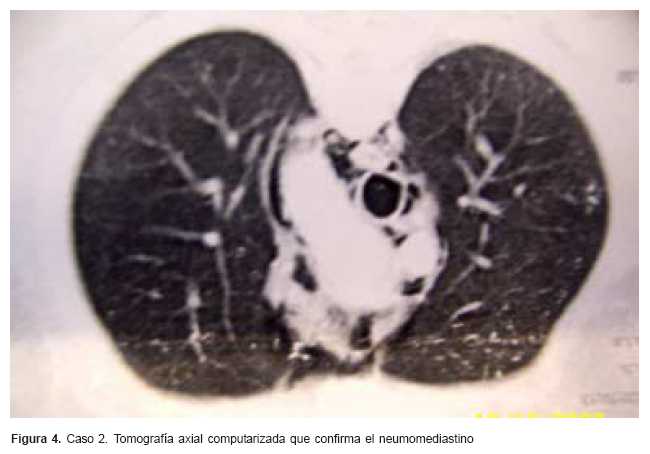

La tomografía axial computarizada (TAC) (figuras 3 y 4) confirma el neumomediastino y permite descartar otras lesiones asociadas, fundamentalmente la coexistencia de un neumotórax.

La tomografía permite descartar la coexistencia de una enfermedad pulmonar de base o un neumotórax asociado, o ambos,(7,8) que haya pasado desapercibido en la radiología previa.